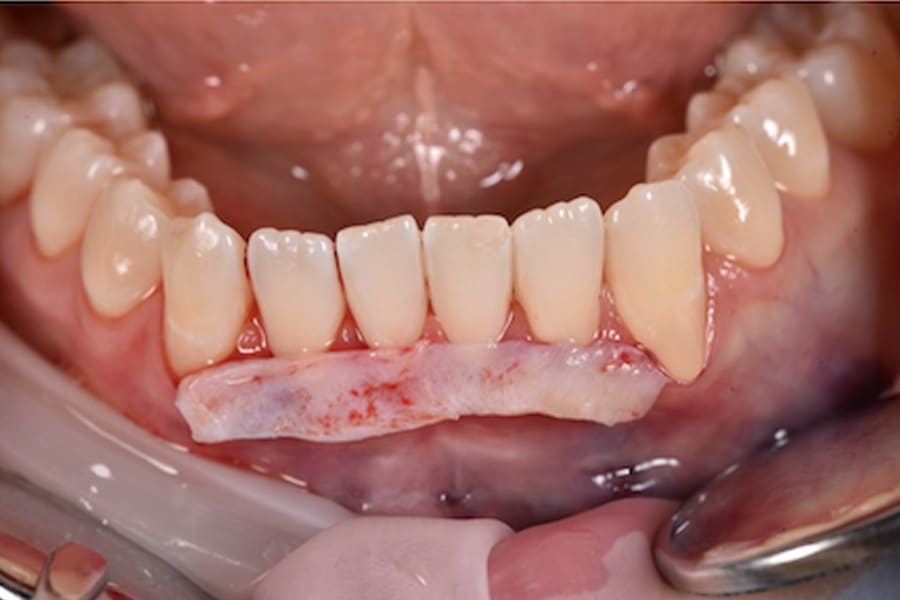

Periodontal Management and Thin Phenotypes

In thin phenotypes with early recessions, minimally invasive tunneling with CTG (with enamel matrix proteins on exposed roots when indicated) can increase soft-tissue thickness and support long-term stability after orthodontic tooth movement.12-16 (Figure 14 through Figure 17)

Periodontium: Enable gentle forces; later, incorporate CTG to thicken the thin phenotype and cover recessions.4-8,12-16